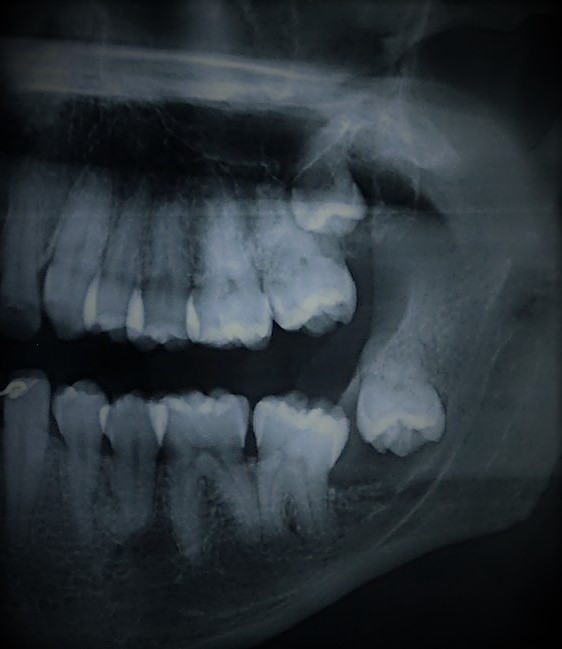

Muitos pacientes apresentam dentes que não irromperam (nasceram) total ou parcialmente, necessitando de procedimentos para tratamento. O procedimento mais comum é a exodontia (remoção) dos sisos (dentes do juízo). Mas existem outros procedimentos que podem ser indicados, como exemplo, o tracionamento de caninos inclusos.

É importante deixar claro que nem todos os sisos precisam ser removidos. As indicações mais comuns são devido a infecções (pericoronarites), cáries, doença periodontal, cistos associados e mordedura da mucosa jugal (bochecha).

Todas essas indicações podem causar desconforto. A definição se o siso está em boa posição e não precisa ser removido deve ser realizada por um cirurgião dentista. Caso indicado a remoção de um ou mais sisos, preferencialmente indica-se realizar na fase final da adolescência ou início da fase adulta, pois suas raízes ainda não estarão totalmente formadas. Mas, não existem limites de idade para remoção de dentes inclusos, quando o procedimento for necessário.